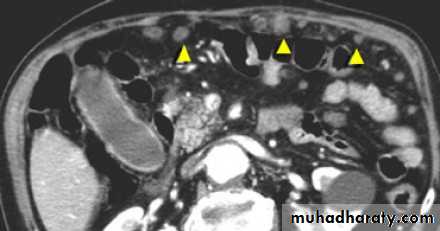

Ascites

Peritoneal cavity and retroperitoneal